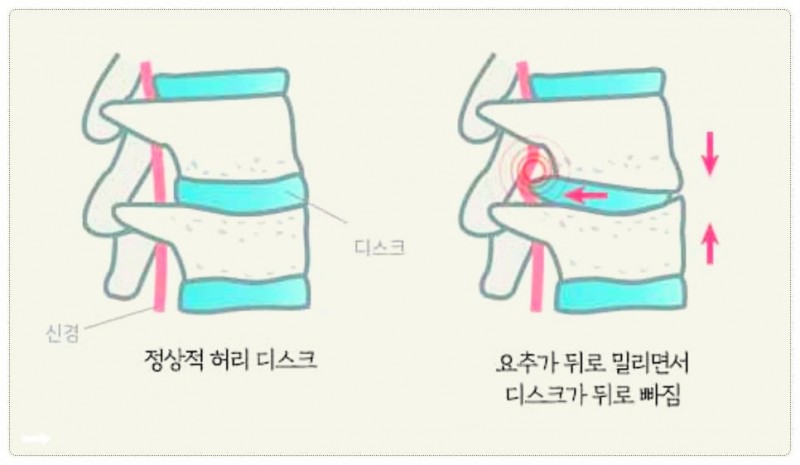

우리 척추 사이에는 푹신한 쿠션 같은 디스크가 있는데요.

이게 뒤로 밀려 나오면서 다리로 가는 신거 전달 길목인 신경을 꾹 누르게 됩니다.

이것이 바로 많은 분들이 고생하시는 방사통의 시작이죠.

수도 호스가 꽉 밟히면 물이 안 나오듯 신경이 눌리면 그 전달 체계에 문제가 생겨 다리가 저리고 힘이 빠지는 거예요.